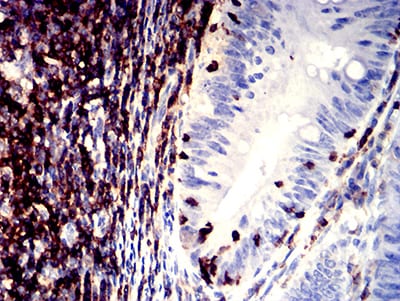

| IHC | 1/50-1/100 | Human,Mouse,Rat |